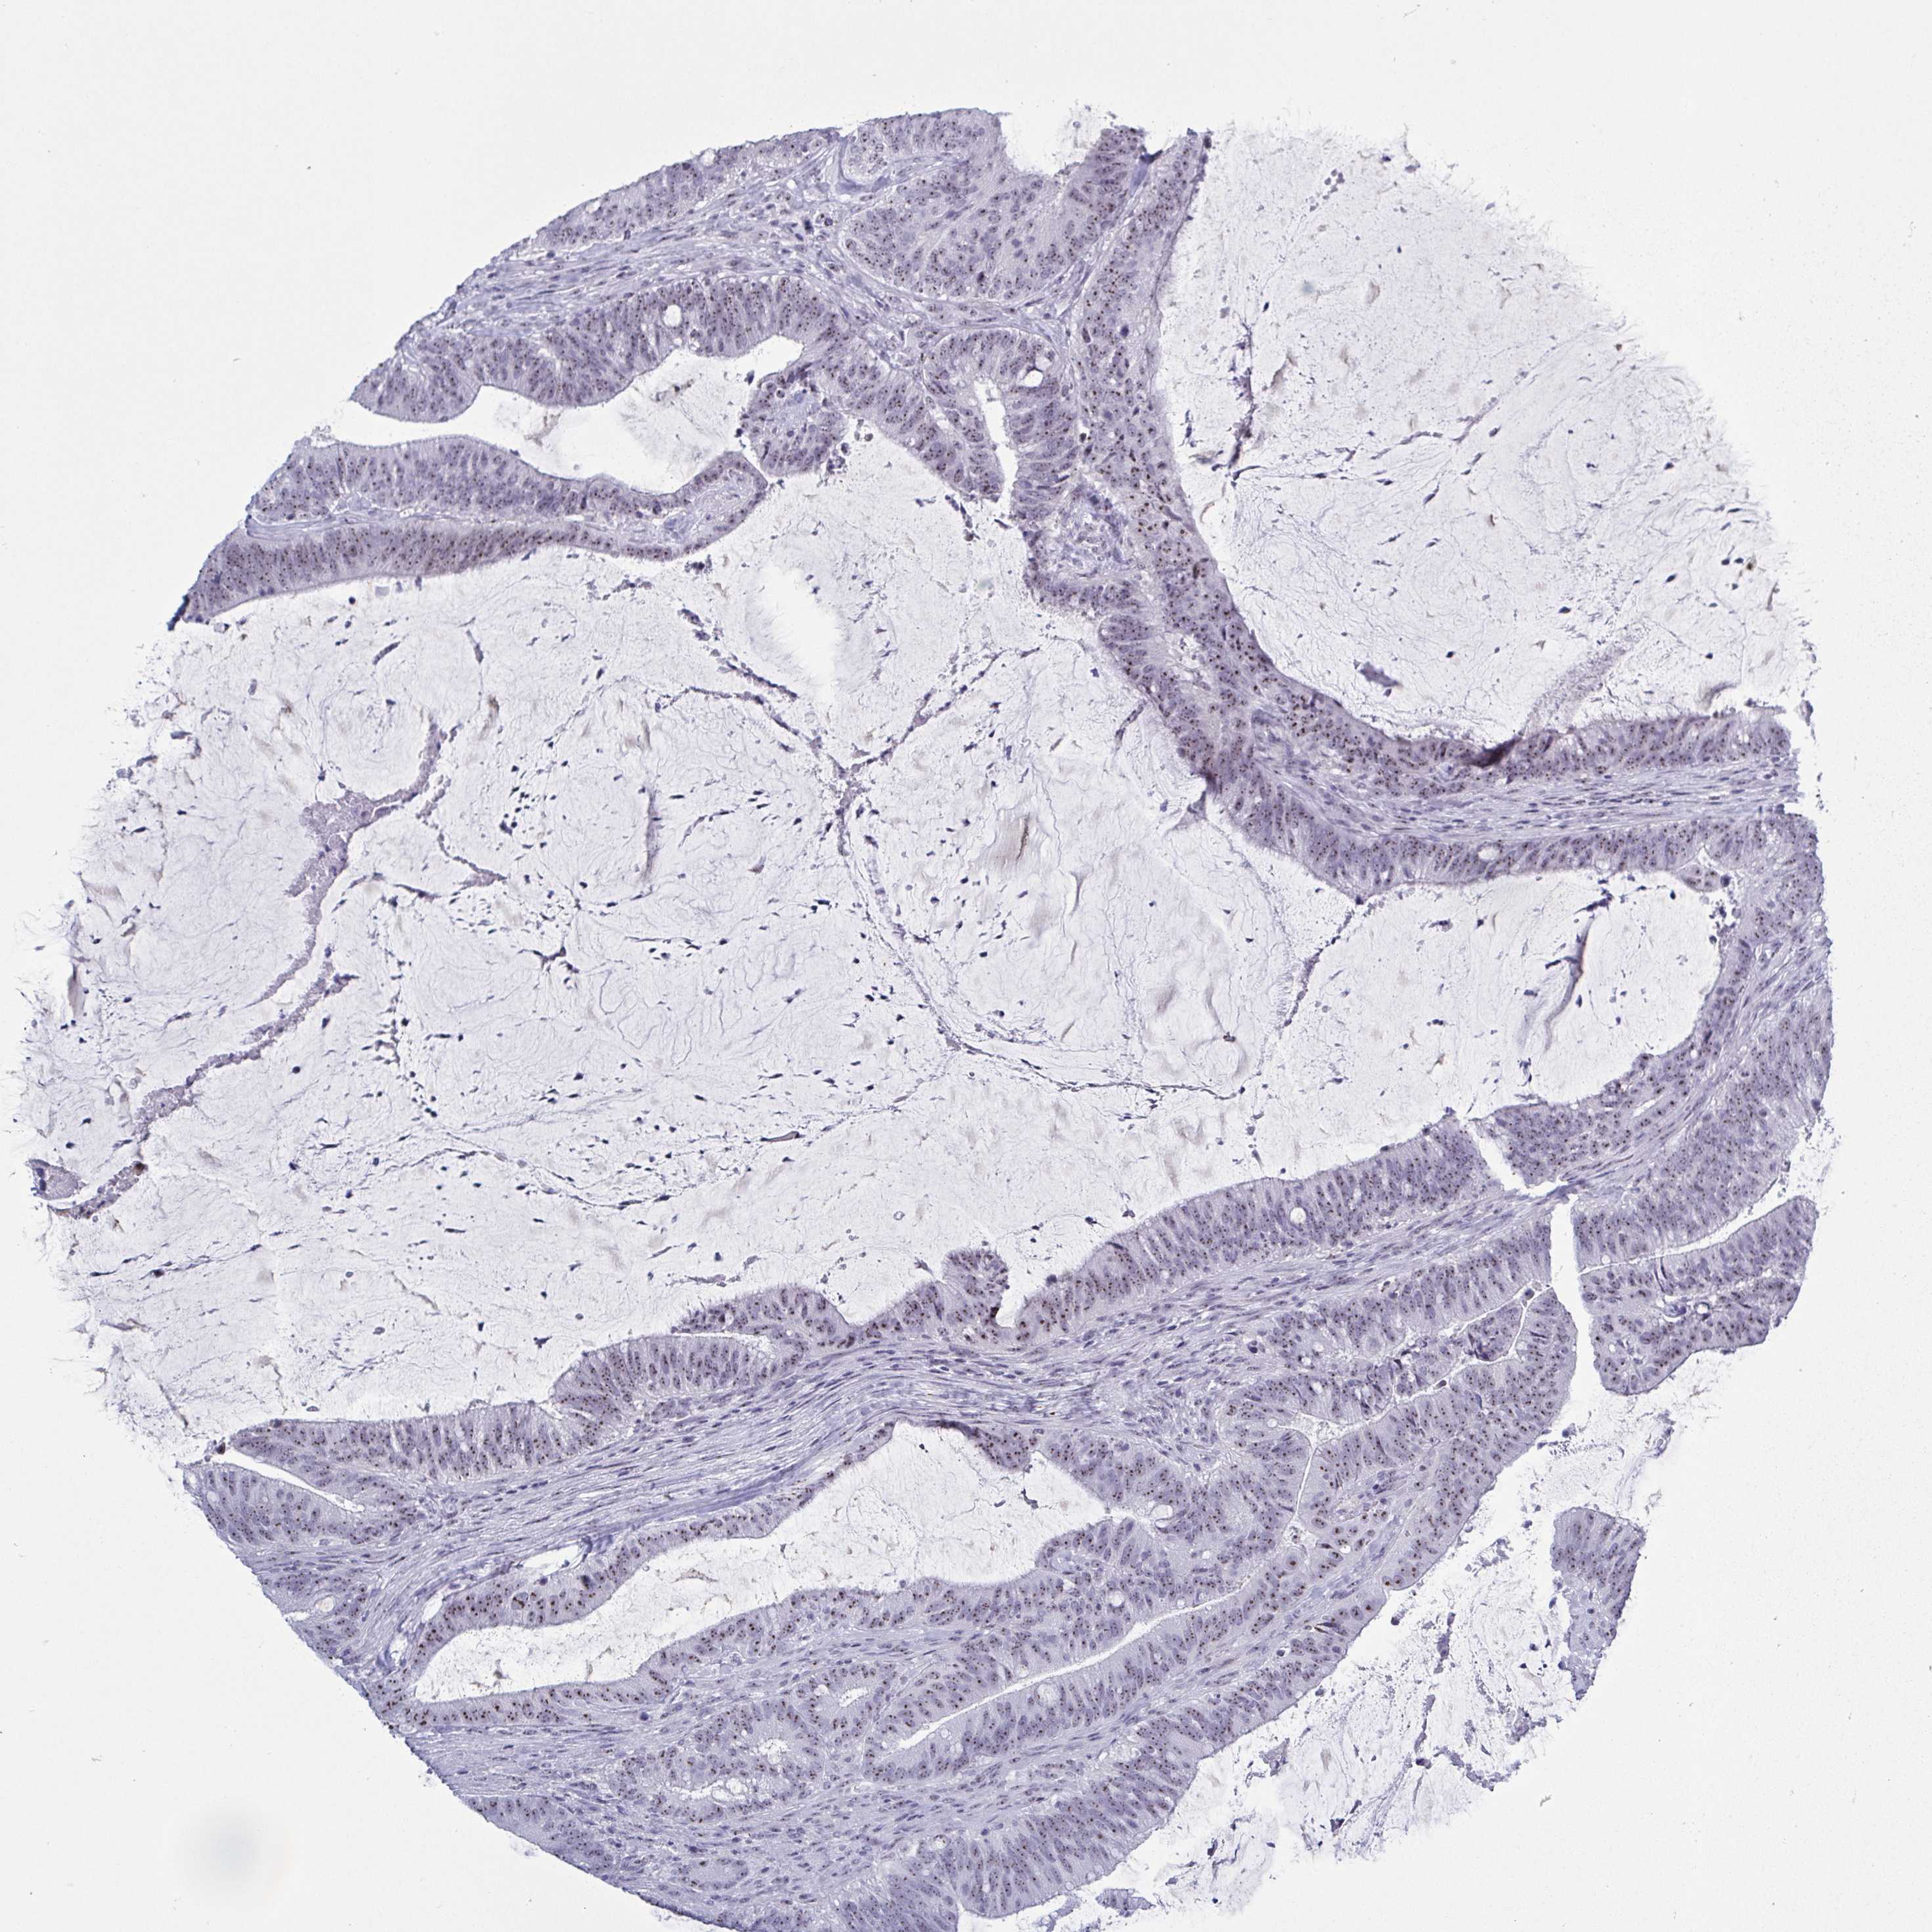

CANCER COLORECTAL CANCER Show tissue menu

Colorectal cancer

Human cancer

Rectum adenocarcinoma